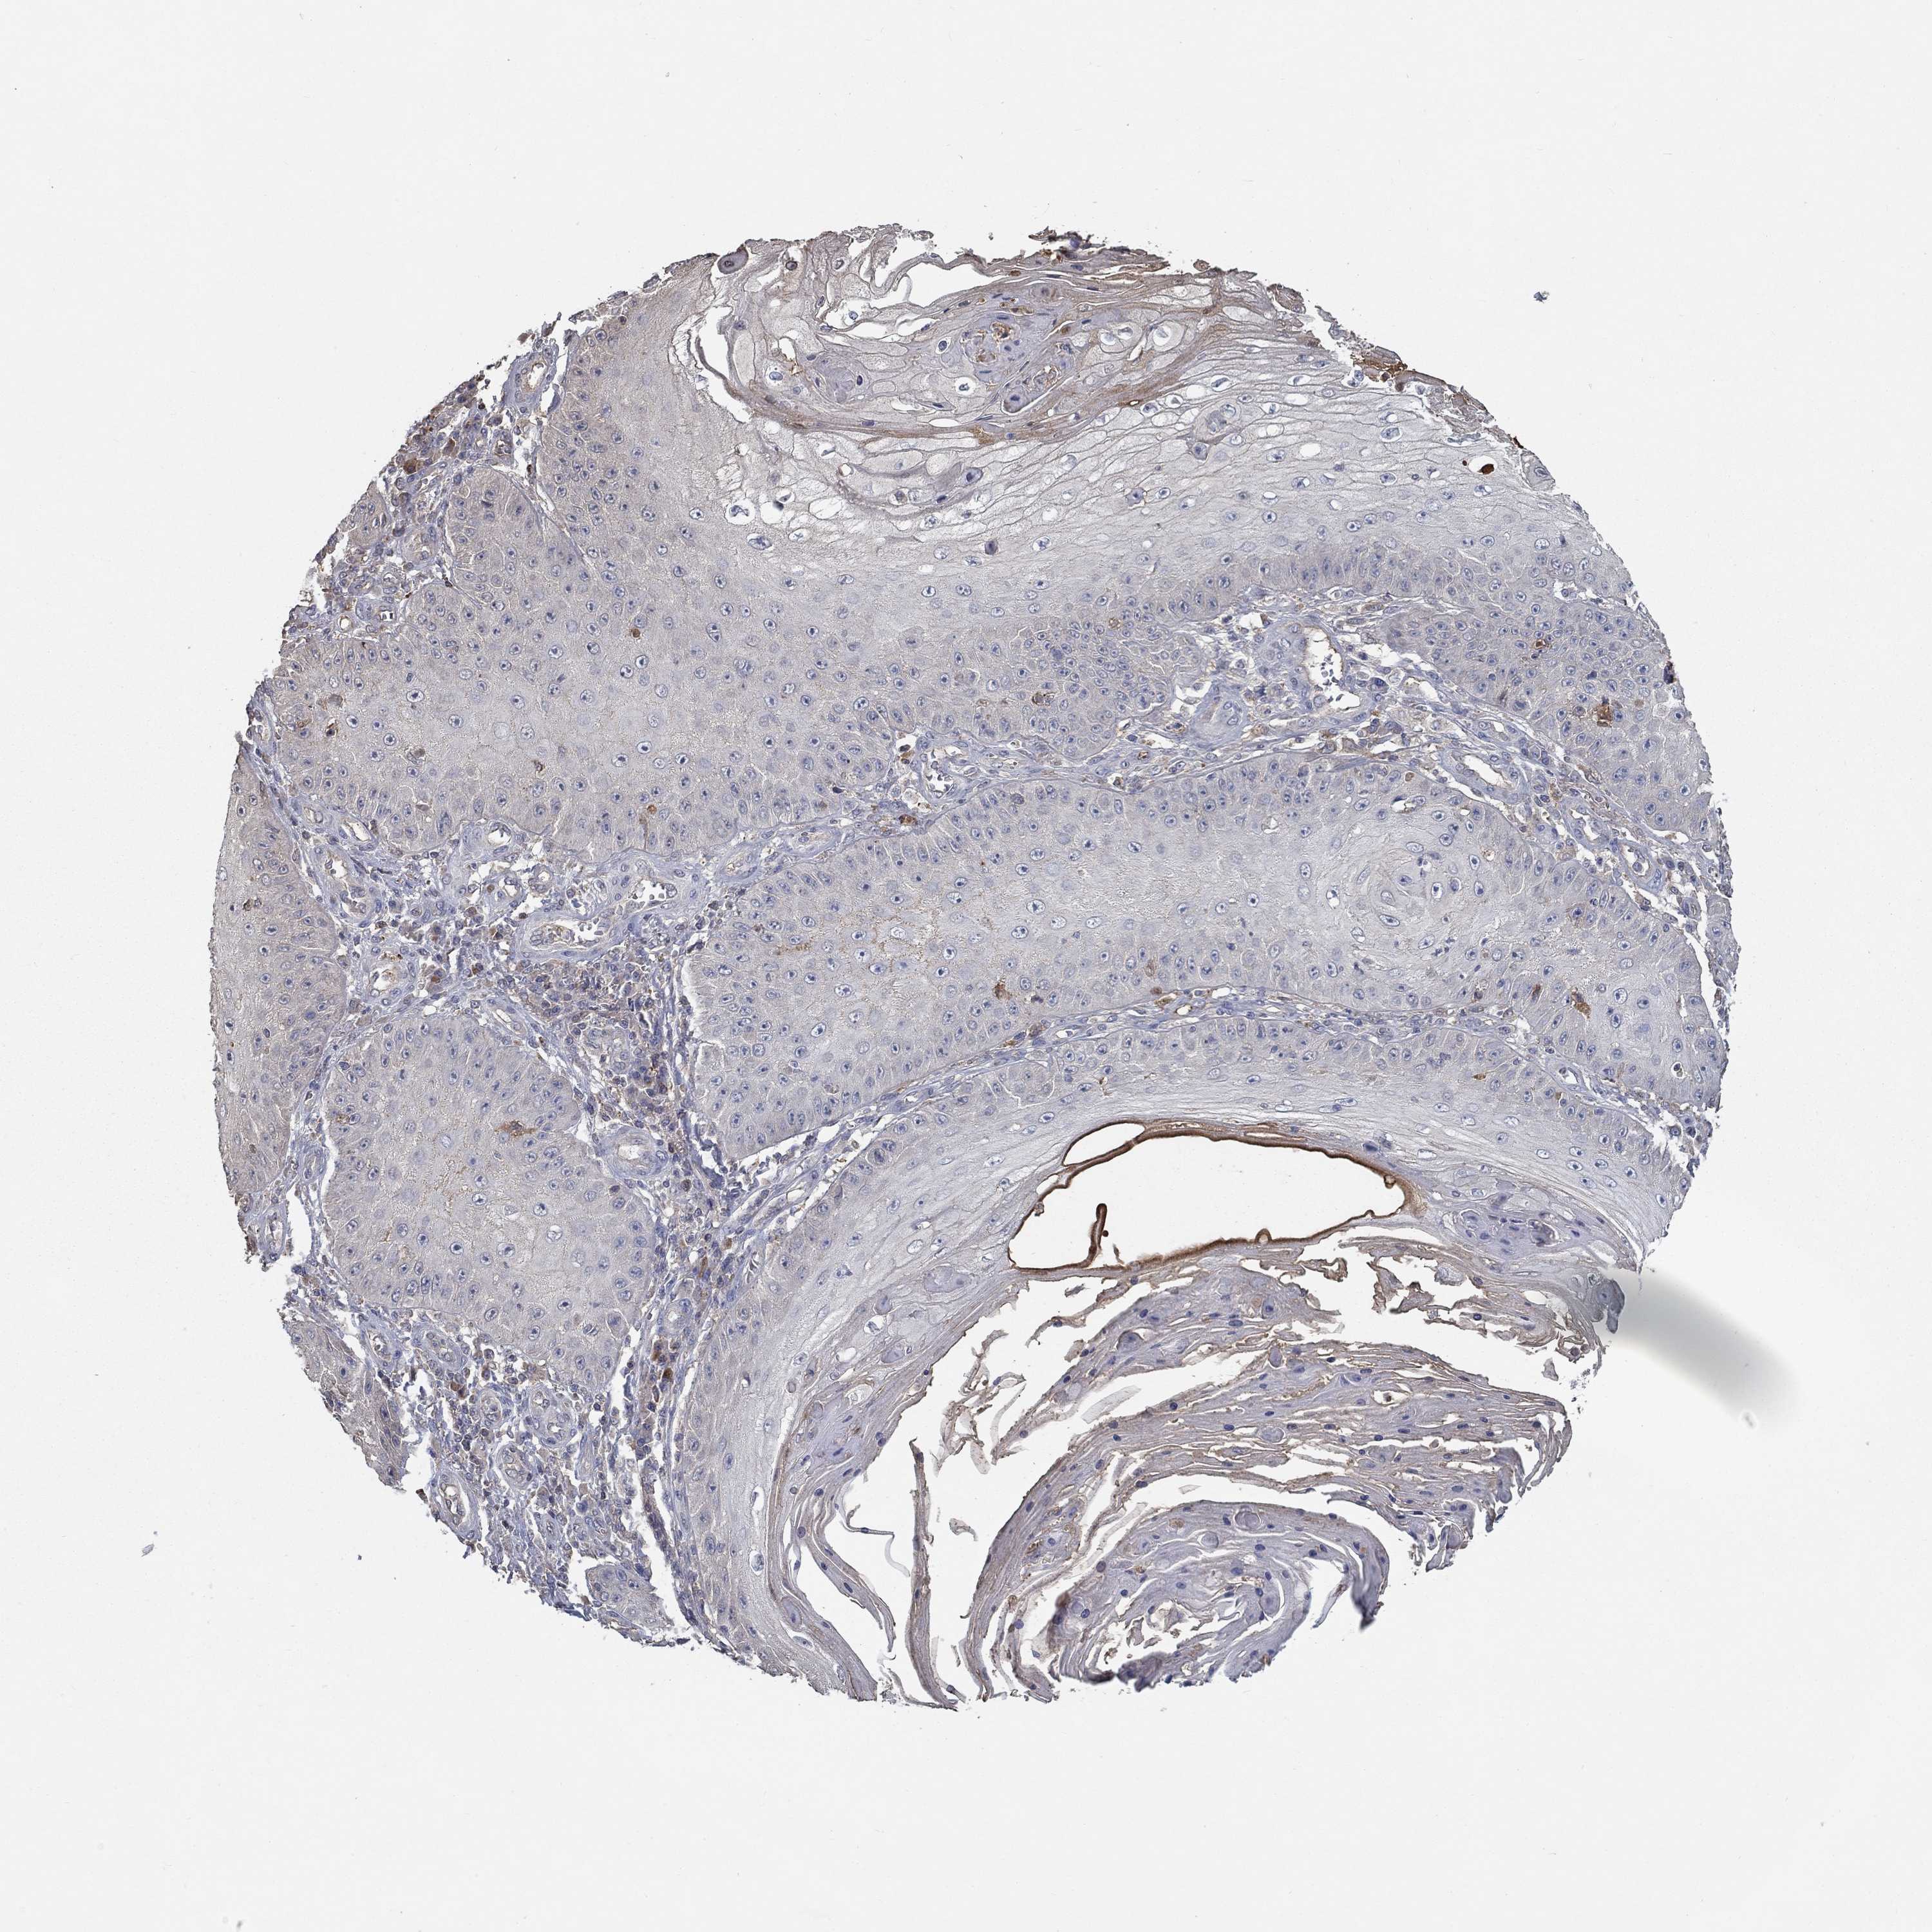

SKIN CANCER - Protein expressioni

A mouse-over function shows sample information and annotation data. Click on an image to view it in a full screen mode. Samples can be filtered based on level of antibody staining by selecting one or several of the following categories: high, medium, low and not detected. The assay and annotation is described here.

Antibody stainingi

Antibody staining in the annotated cell types in the current human tissue is reported as not detected, low, medium, or high, based on conventional immunohistochemistry profiling in selected tissues. This score is based on the combination of the staining intensity and fraction of stained cells.

Each image is clickable and will lead to virtual microscopy that enables deeper exploration of all samples and also displays staining intensity scores, fraction scores and subcellular localization as well as patient and tissue information for each sample.

Antibody HPA071391

Antibody CAB013120

Basal cell carcinoma

Squamous cell carcinoma, NOS